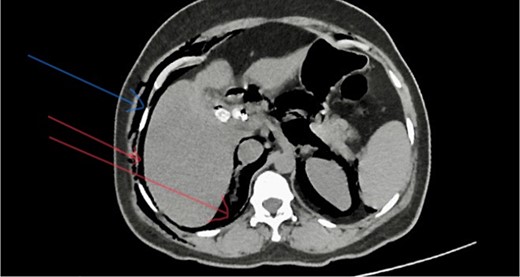

She has undergone a semi-elective ERCP in a semi-prone position, under sedation with propofol target-controlled infusion. Major papillae identified with side viewing endoscopy. Guidewire was inserted into CBD, and a cholangiogram was done. It showed dilated CBD up to 1.3 cm, mild dilated hepatic ducts, and a large radiolucent area in the distal CBD (around 1.5 cm). Sphincterotomy was done with a sphincterotome, and the ampulla was dilated up to 1.5 cm with a balloon dilator. Then, a balloon retrieval was attempted and failed, probably due to a stone sticking to the CBD wall. Then, a mechanical lithotripter was used to break the stone, but it failed, damaging the instrument. During the procedure, her oxygen saturation dropped to 75–80%, and she developed surgical emphysema in the face, neck, and upper chest region. In addition, she developed abdominal distention as well. Immediately, she underwent CBD stenting with a 12-cm, 10 French Gauge double pigtail biliary stent and changed her position to supine. Then, she was intubated with rapid sequence induction, and a nasogastric tube was inserted and transferred to the surgical intensive care unit. Post-ERCP, non-contrast computed tomography (NCCT) of the abdomen and chest showed extensive pneumo-peritoneum and retroperitoneal gas with subcutaneous emphysema (Figs 2 and 3). There was no evidence of air leakage on NCCT and no clinical features of peritonitis on subsequent days. So she was managed non-surgically with nasogastric tube (NG), nil by mouth, intravenous fluids with intravenous antibiotics. Clear fluid was started after 24 hours slowly via NG.

Post-ERCP NCCT abdomen shows pneumo-peritoneum (red arrow), pneumo-retroperitoneum, and subcutaneous emphysema (blue arrow)